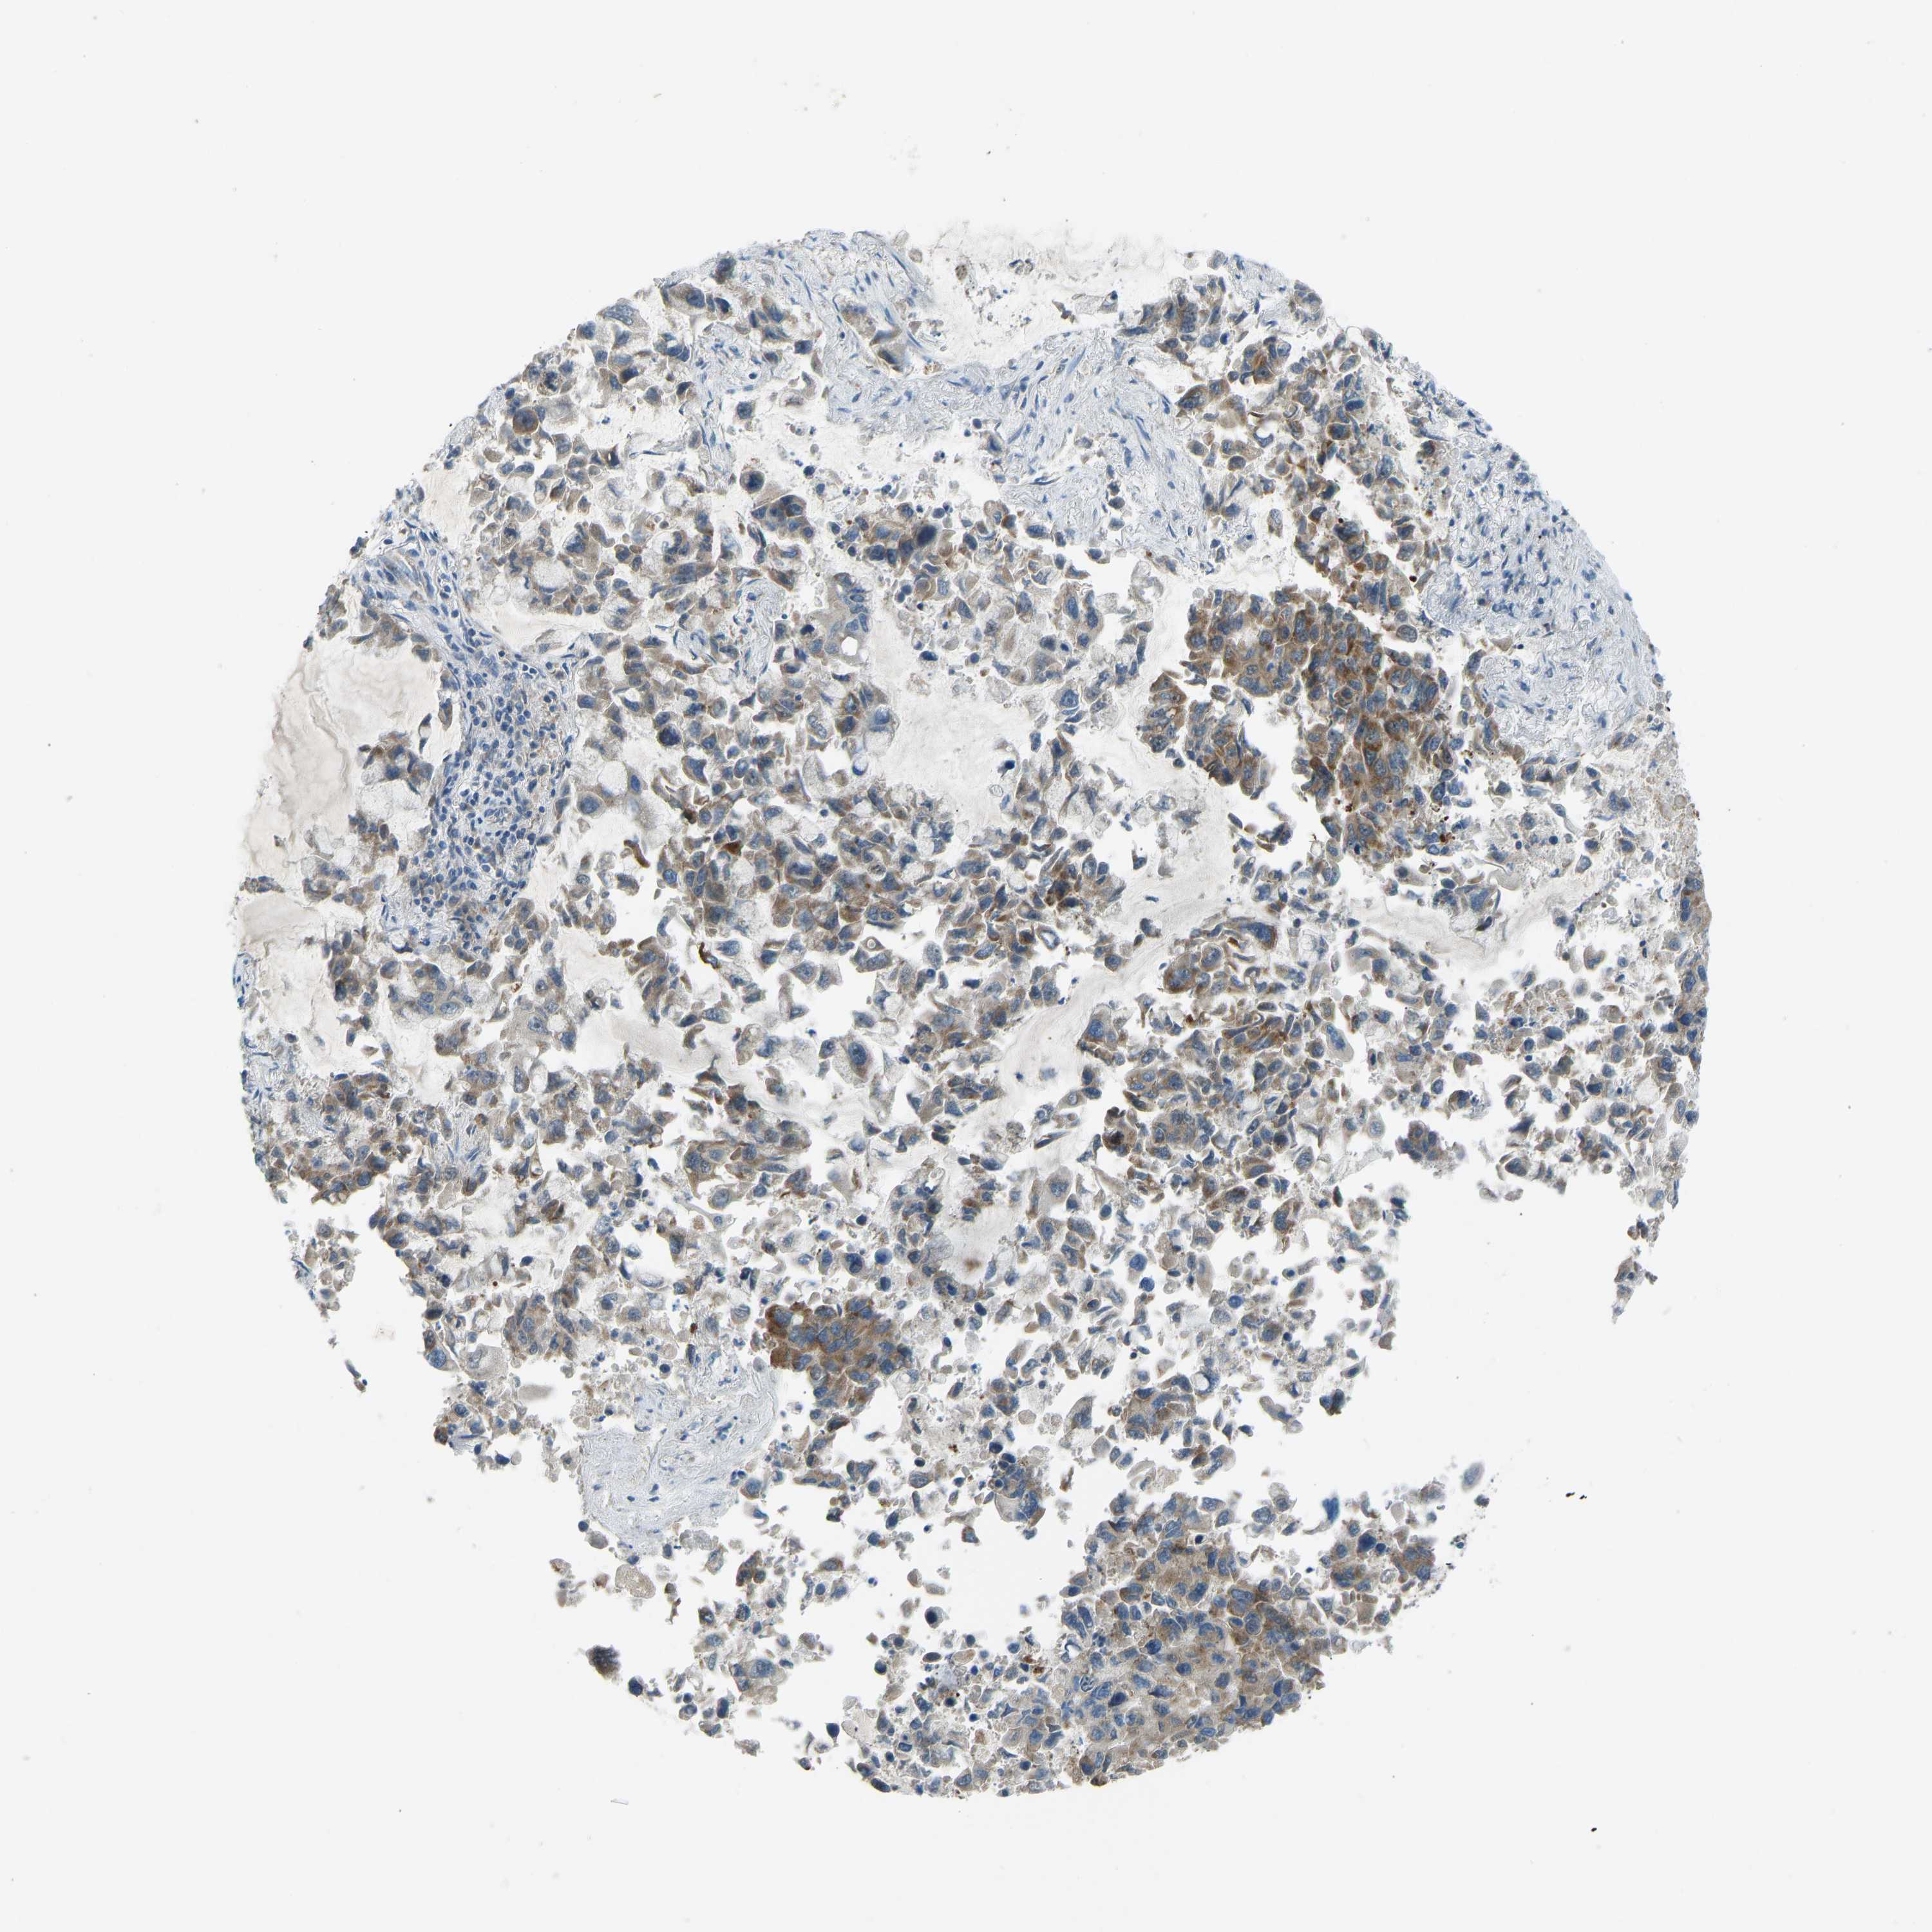

CANCER LUNG CANCER Show tissue menu

LUAD TCGA LUAD VALIDATION LUSC TCGA LUSC VALIDATION PROTEIN LUAD CPTAC PROTEIN LUSC CPTAC PROTEIN EXPRESSION